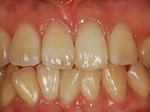

術前

→

術後